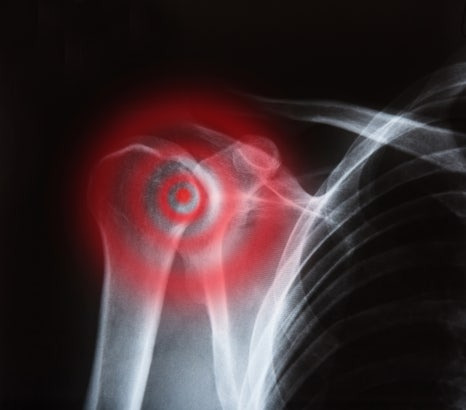

수원회전근개파열 어깨 힘줄 손상 증상과 치료

최근 진료실에서 팔을 들 때 어깨가 찢어지는 것처럼 아파요, 밤에 누우면 어깨가 더 아파서 잠을 못 자겠다는 이야기를 하는 분들이 적지 않습니다. 이런 증상이 반복된다면 회전근개파열과 같은 어깨 힘줄 손상을 의심해 볼 필요가 있습니다. 오늘은 어깨힘줄손상증상이 어떤 식으로 나타나는지, 그리고 어깨힘줄손상치료는 어떻게 진행될 수 있는지 차근차근 알아보겠습니다.

어깨 관절은 팔뼈와 견갑골이 만나 형성되는 구조입니다. 이 관절이 안정적으로 움직이기 위해서는 여러 근육과 힘줄이 함께 작용해야 합니다. 회전근개는 극상근, 극하근, 견갑하근, 소원근이라는 네 개의 근육과 힘줄로 이루어진 구조입니다. 이 조직은 어깨 관절을 감싸면서 팔을 들어 올리는 동작과 회전 움직임을 안정적으로 유지하는 역할을 합니다.

쉽게 말해 회전근개는 어깨 관절이 흔들리지 않도록 잡아주는 핵심 안정 장치라고 생각하시면 됩니다. 하지만 반복적인 사용이나 외부 충격 혹은 퇴행성 변화가 겹치면 이 힘줄이 손상되거나 찢어질 수 있습니다. 이런 상태를 회전근개파열이라고 합니다.